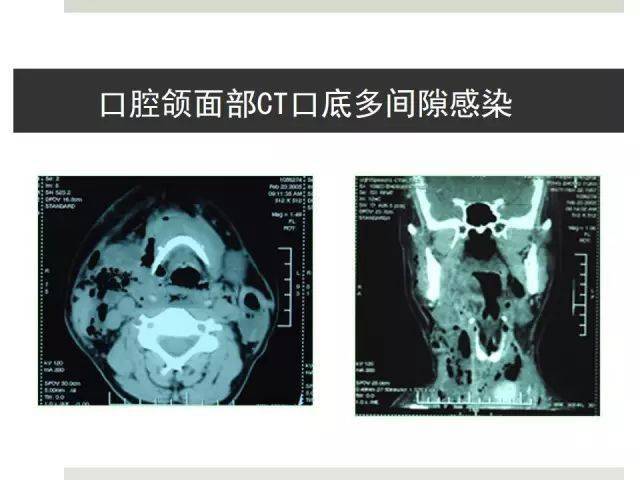

口底多间隙感染_口底多间隙感染死亡

图片尺寸628x664